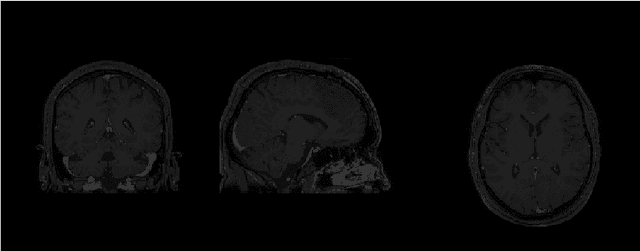

Abstract:Magnetic Resonance Imaging (MRI) is the most commonly used non-intrusive technique for medical image acquisition. Brain tumor segmentation is the process of algorithmically identifying tumors in brain MRI scans. While many approaches have been proposed in the literature for brain tumor segmentation, this paper proposes a lightweight implementation of U-Net. Apart from providing real-time segmentation of MRI scans, the proposed architecture does not need large amount of data to train the proposed lightweight U-Net. Moreover, no additional data augmentation step is required. The lightweight U-Net shows very promising results on BITE dataset and it achieves a mean intersection-over-union (IoU) of 89% while outperforming the standard benchmark algorithms. Additionally, this work demonstrates an effective use of the three perspective planes, instead of the original three-dimensional volumetric images, for simplified brain tumor segmentation.